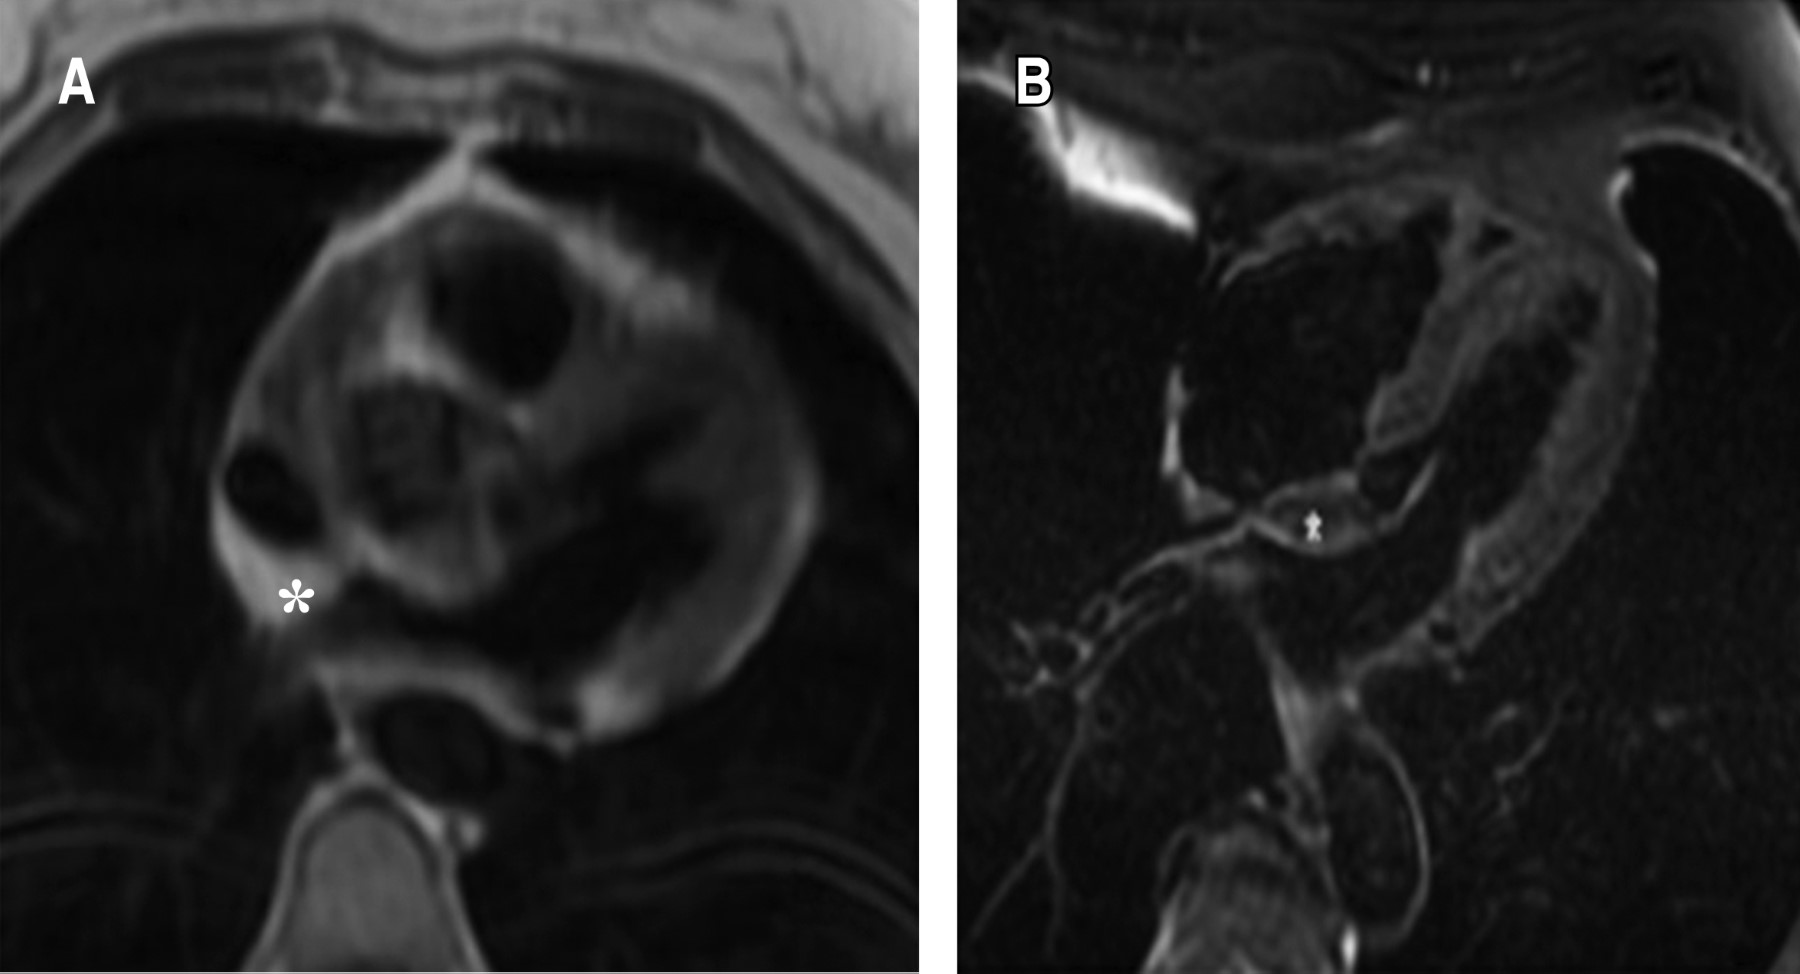

Palpitaciones como manifestación de hiperplasia lipomatosa del tabique interauricular: reporte de caso y revisión de literatura

La hipertrofia lipomatosa del tabique interauricular se reconoce cada vez más y debe considerarse como parte del diagnóstico diferencial de uier tumor cardiaco. Presentamos el caso de un paciente de 70 años que acudió al servicio ambulatorio por palpitaciones. El ecocardiograma transtorácico (ETT) detectó engrosamiento del septo interauricular de predominio proximal con respecto de la fosa ovalis. El diagnóstico fue confirmado por resonancia magnética cardiaca. En tales casos, la opinión de un cardiólogo experto en imagen cardiaca ayudaría a evitar un diagnóstico erróneo y una intervención innecesaria. Esta condición es más común de lo que se pensó inicialmente y sigue siendo poco reconocida por la mayoría de los médicos.

Figura 2